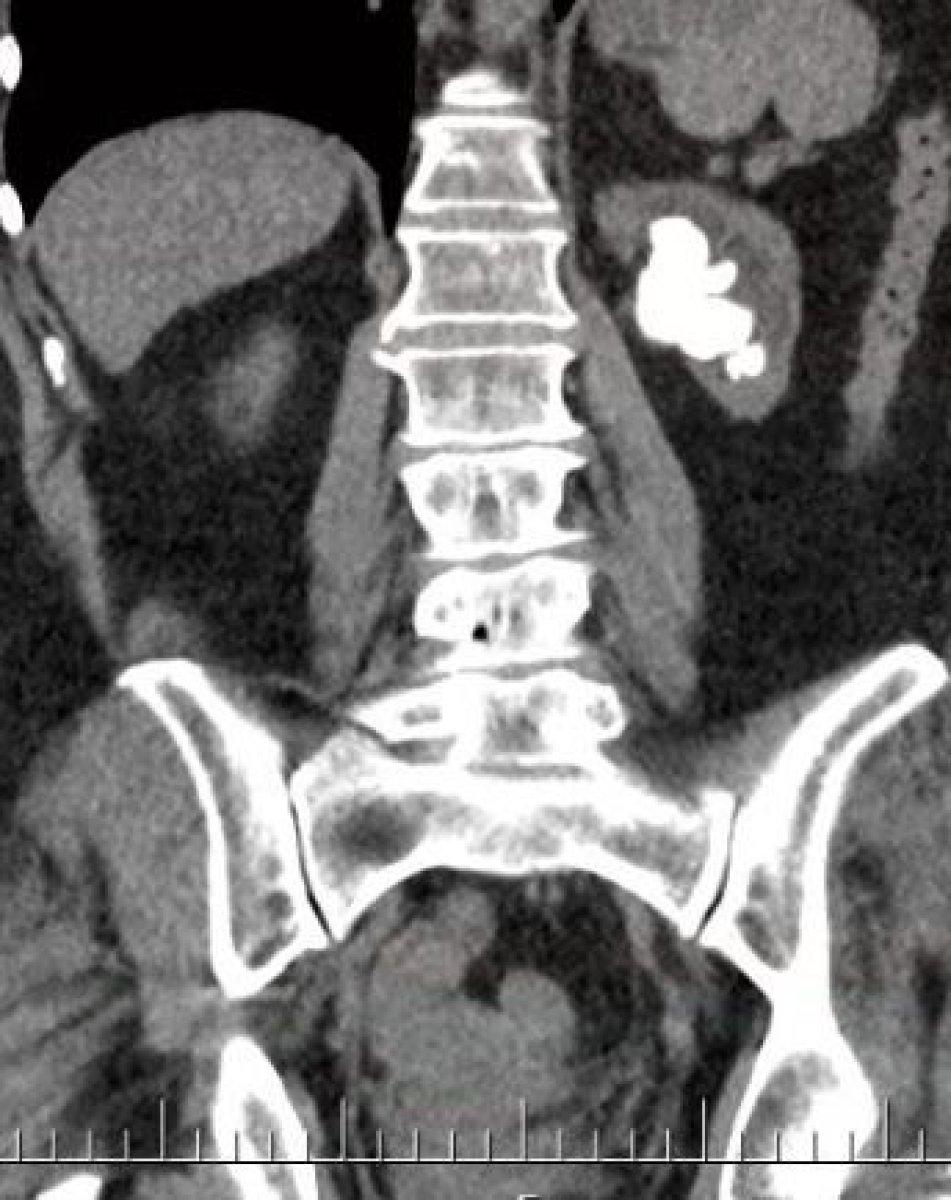

Nesibe Işık’ın yapılan tetkik ve kontrollerinde, sol böbreğinde büyük bir taş parçası olduğu tespit edildi.

Hastanın böbreğinin içerisini tamamen dolduran, bilimsel olarak ‘geyik boynuzu’ olarak adlandırılan dev böbrek taşını sıkıntısız bir şekilde aldıklarını belirten Dr. Sancak, “Hastamızın böbrek fonksiyonları da sınırda çalışmaktaydı. Bu nedenle hastamıza ve böbreğe daha az hasar verecek, Çanakkale’de ilk kez uygulanan ‘Miniperk’ yöntemini kullanarak, küçük bir delikten böbrek taşlarının tamamını temizledik. Günümüzde teknolojik gelişmeler ve bilimsel yöntemler hep daha az zarar veren, daha küçük kesi ile yapılan cerrahilere doğru değişim göstermekte. Biz de ÇOMÜ Hastanesi Üroloji Anabilim Dalı olarak, bu teknolojiye ayak uydurma çabasındayız. Hastamızın şu an sağlık durumu gayet iyi, çok kısa zamanda toparlandı.” dedi.